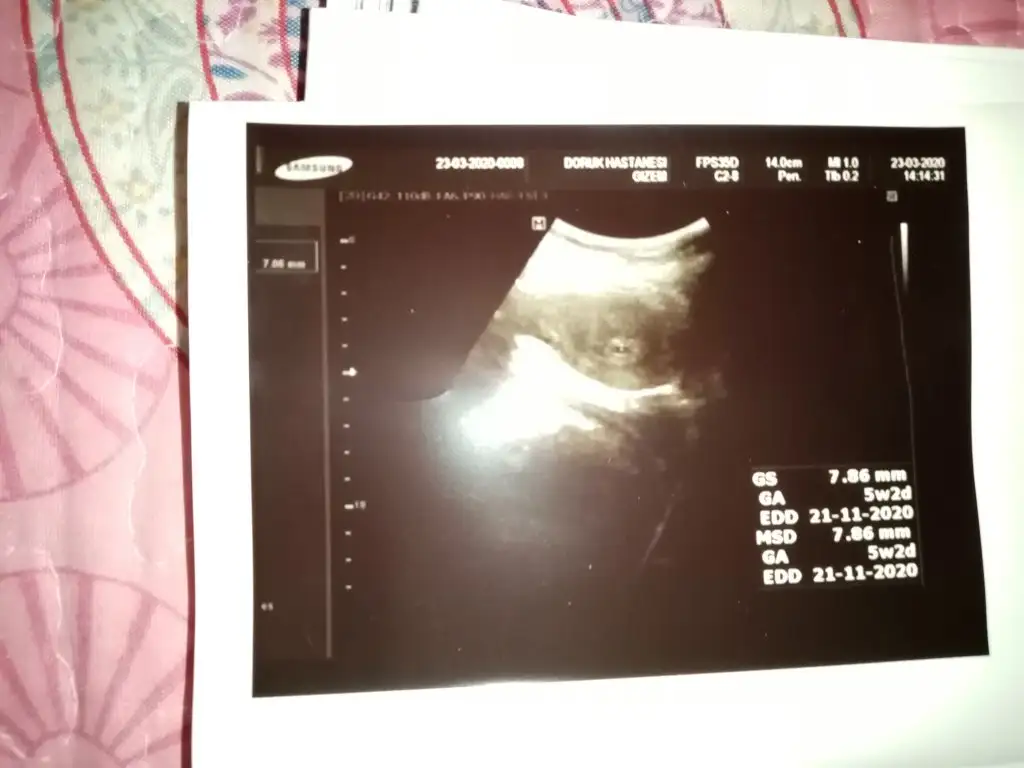

Rica etsem bana da bir tahmin de bulunabilir misiniz

Eklentiler

• 20200312_090552~2.webp

20200312_090552~2.webp

24,3 KB · Görüntüleme: 148

• 20200401_090222~3.webp

20200401_090222~3.webp

20,9 KB · Görüntüleme: 151